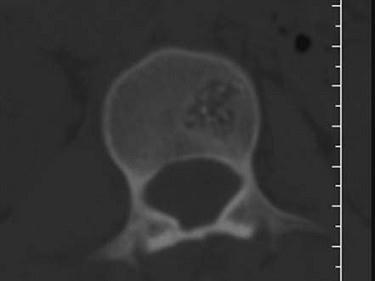

问题 根据所提供的图像,选择最可能的诊断 ( )

选项 A、退行性变 B、骨质疏松 C、多发性骨转移 D、骨血管瘤 E、骨结核

答案 D